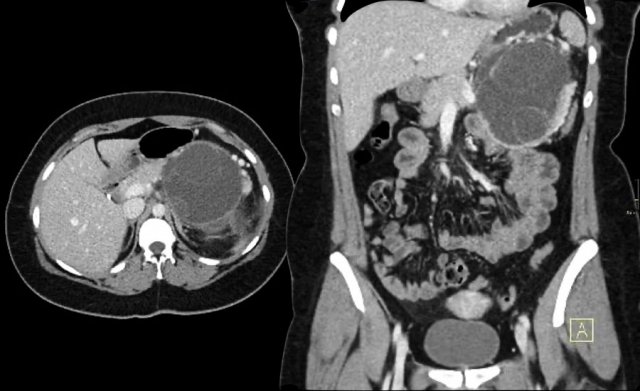

The images show a serous cystic neoplasm (SCN) on a CT.

MRI better shows the central scar.

There are cases when CT can be helpful, since it better depicts a central calcification in SCN or peripheral calcification in a mucinous cystic neoplasm (MCN).

CT images of a mucinous cystic neoplasm with septations and peripheral calcifications.